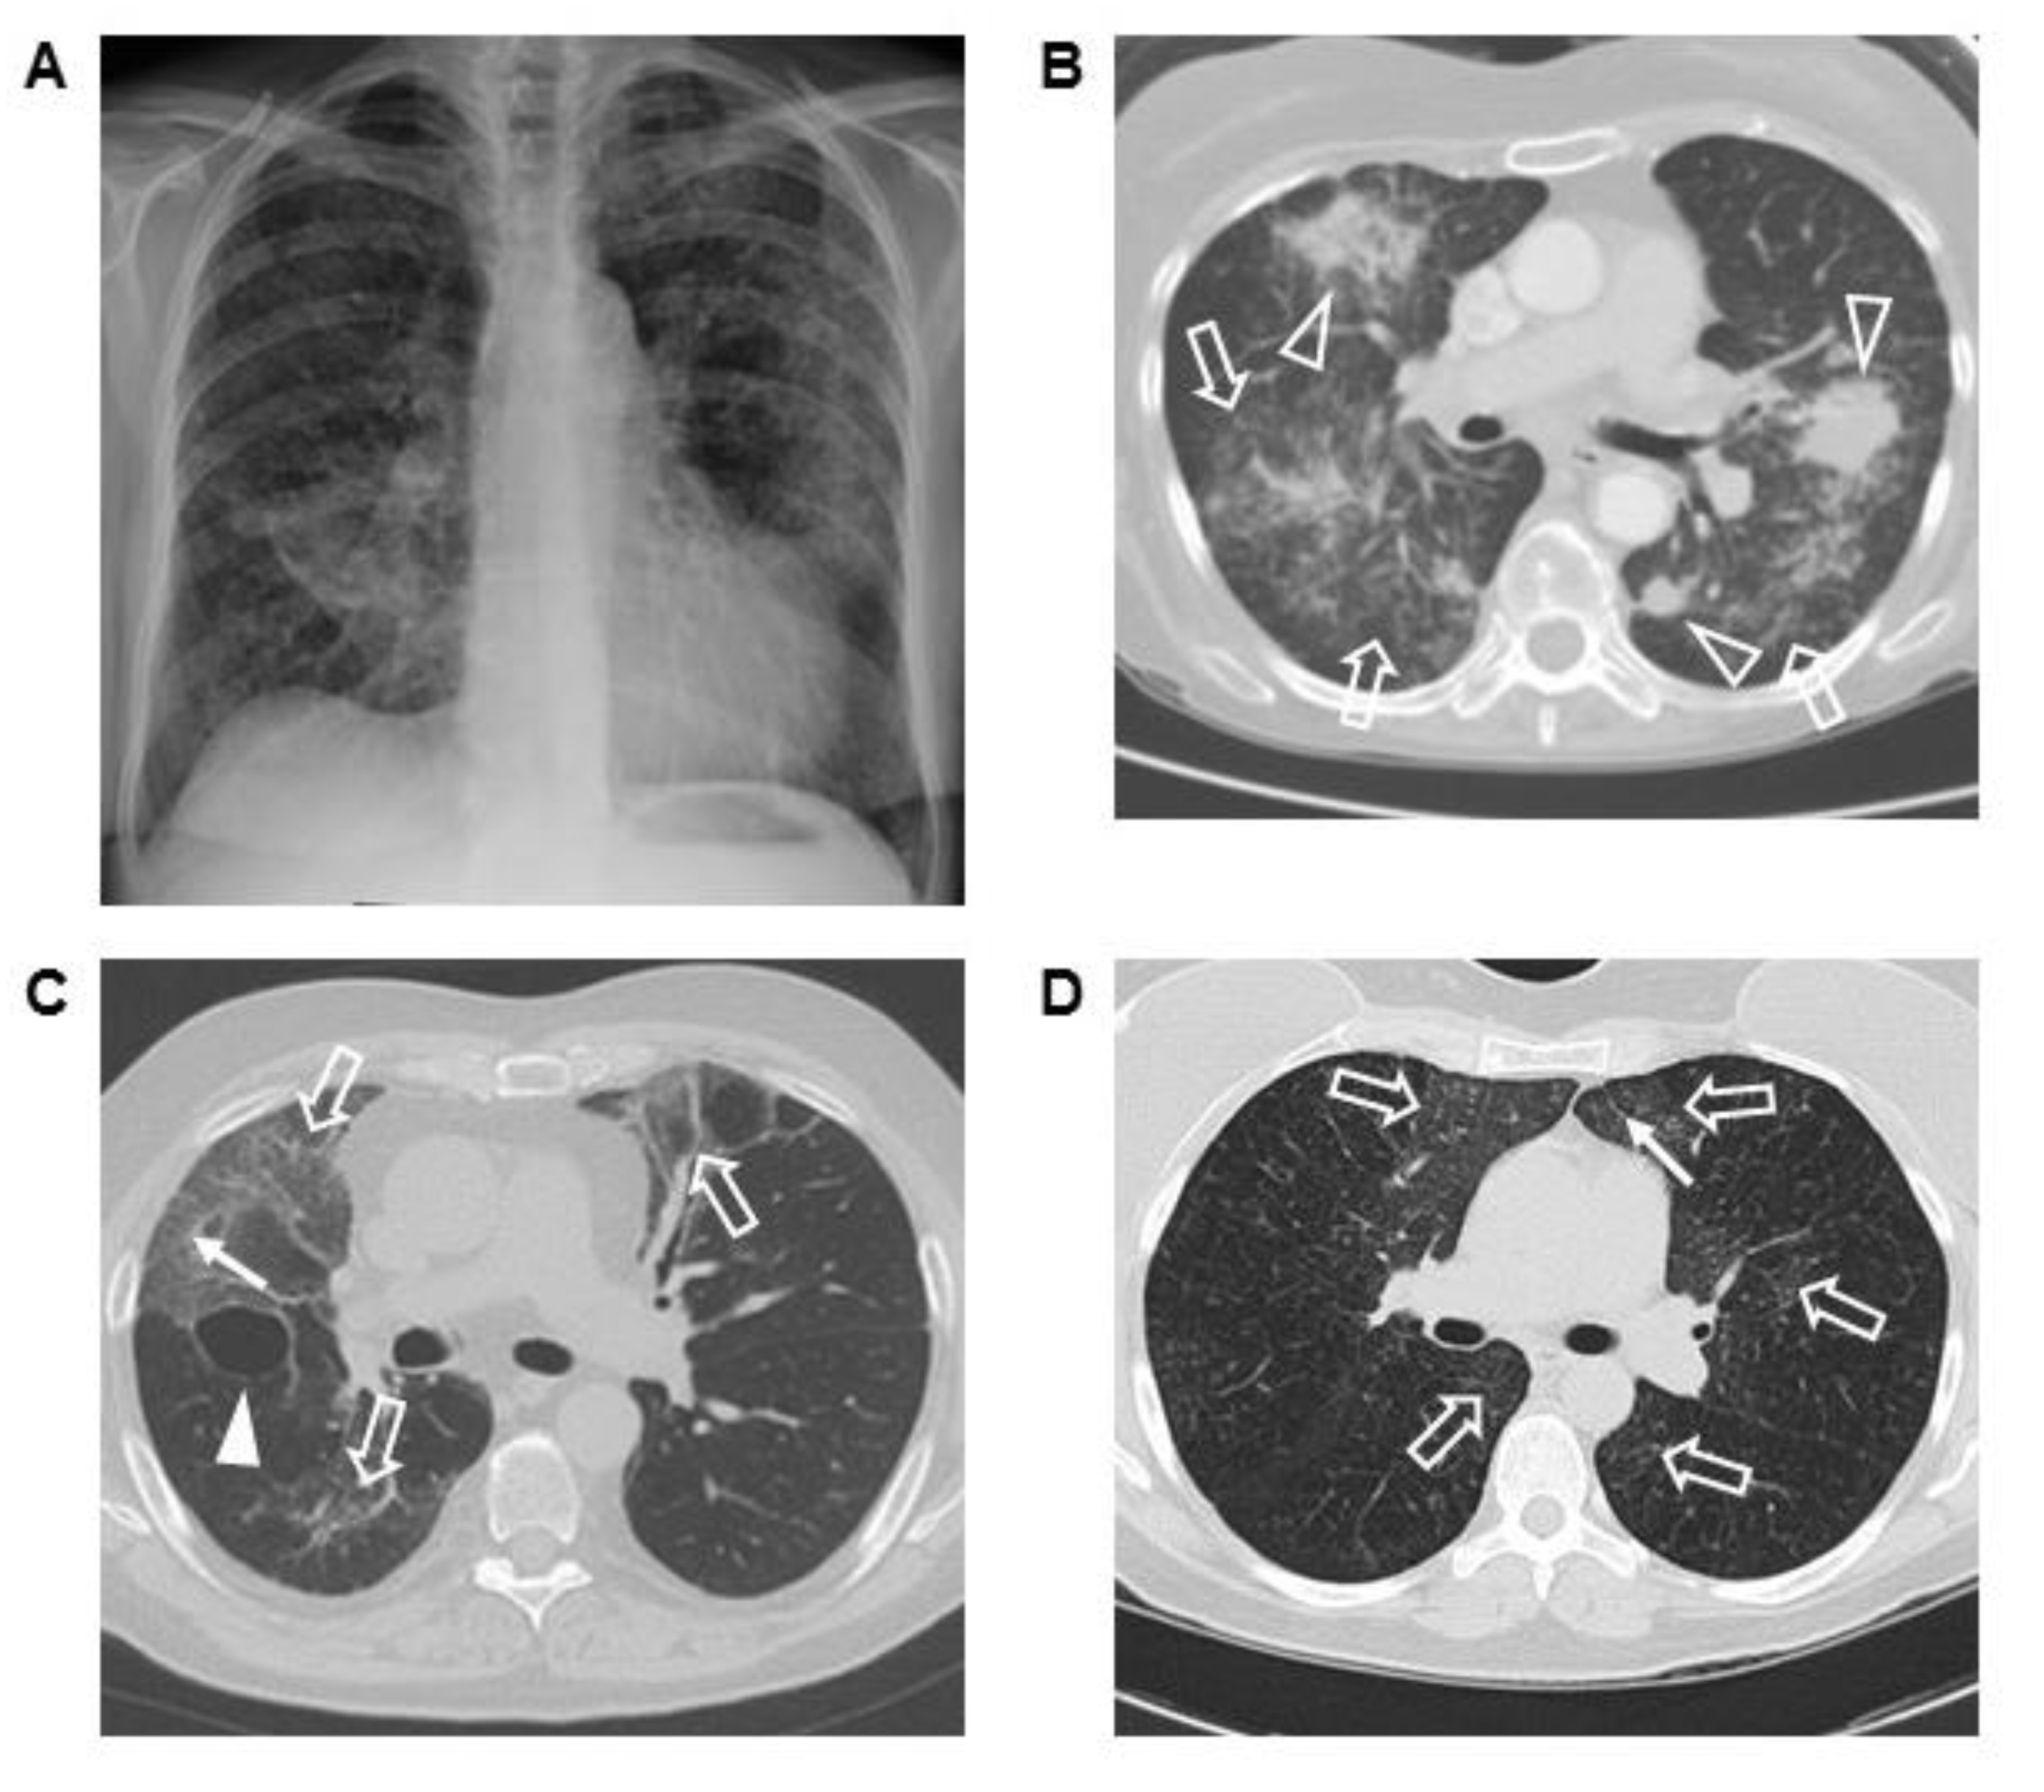

Three ECD patients with severe ILD had chest imaging and lung biopsies. Chest radiograph and CT scan from one patient showed bilateral interstitial lung disease with ground-glass opacification, parenchymal masses, and airspace disease (Figure 2A,B). Sections of the open lung biopsy showed heterogeneous involvement of the lung parenchyma with normal areas interrupted by nodular fibrotic interstitial expansion lined by type II pneumocytes and infiltrated by histiocytes (Figure 3A,B). In addition to histiocytic infiltration, there was a mild lymphoplasmacytic infiltrate. The histiocytes stained with CD68, CD163, and S-100 and showed evidence of emperipolesis. Factor XIIIa, CD1a, and langerin were negative.

Figure 2.

Posteroanterior chest radiograph (A) and representative computer tomography (CT) scan of the chest image (B) from a patient with Erdheim–Chester disease (ECD) and severe interstitial lung disease (ILD). Multiple bilateral consolidated masses (open arrowheads) with ground-glass infiltrates (open arrow) are found (B). Ground-glass infiltrates, reticulations (arrow), and a right lung cyst (solid arrowhead) are shown in another patient with ECD and severe ILD (C). Diffuse ground-glass opacification and reticulations are demonstrated in a third patient (D).

Another ECD patient had bilateral ground-glass infiltrates as the primary radiographic finding; peripheral reticulations and a lung cyst were also seen (Figure 2C). Sections from the lung biopsy showed extensive interstitial fibrosis. In some areas, the fibrotic pattern mimicked a non-specific interstitial pneumonia pattern with uniform fibrotic widening of alveolar septa, while other areas showed a usual interstitial pneumonia pattern with temporally heterogeneous fibrosis and fibroblastic foci (Figure 3C,D). The interstitial inflammation varied from mild to moderate infiltrates of lymphocytes and plasma cells, and the fibrotic septa were covered with type II pneumocytes. Collections of pigmented alveolar macrophages filled alveolar spaces, while the interstitial histiocytes were stained with antibodies to CD68, CD163, and factor XIIIa. The histiocytes were negative for S-100 protein and CD1a. This patient developed progressive ILD and died due to respiratory insufficiency.

The chest CT scan of a third patient with ECD and severe ILD showed diffuse ground-glass opacities and subpleural reticulations (Figure 2D). Histopathological evaluation of the open lung biopsy showed dense subpleural, peribronchial, and septal fibrosis, with intervening areas of normal lung (Figure 3E,F). Fibroblast foci were not apparent, but the fibrotic septa were lined by type II pneumocytes. The inflammatory infiltrate was sparse except for scattered lymphoid aggregates located adjacent to bronchioles or in the fibrotic areas. The histiocytes within the fibrosis stained diffusely for both CD163 and factor XIIIa (Figure 3G,H), and focally for S-100 protein. Langerin and CD1a were negative in the histiocytes, although both identified cells near the lymphoid aggregates. BRAF V600E was detected in sections from the lung biopsy.